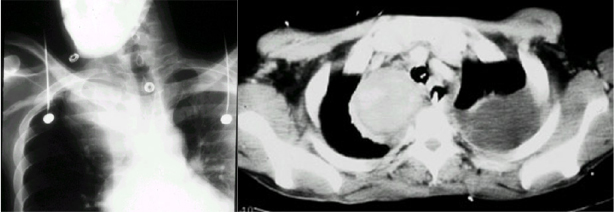

Bei diesem Patienten hat der Chirurg nicht nur auf die obligatorische Durchleuchtng verzichtet, sondern auch noch die ganzen 50 cm Plastikschlauch, die in der Packung sind, ungekürzt in den Patienten geschoben, obwohl der Abstand von der Punktionsstelle bis zur Cava/Vorhofgrenze, wo die Katheterspitze liegen soll, nur 10-12 cm beträgt. Dem Patienten wurden mehrere Zyklen Chemotherapie ins Hirn infundiert, bis die resultierende Sinusvenenthrombose zur Entdeckung der Fehllage führte.

- Pneumothorax bei 5-15%.

- Arterienpunktion (A. carotis oder subclavia der Gegenseite) mit Mediastinalhämatom, Hämatothorax, Intimadisektion/Apoplex bei 10%.

- Pinch off Syndrom bei 2%. Dabei wird der Katheter zwischen 1. Rippe und Clavicula abgeschert. Es kommt zuerst zur Extravasation bei Injektionen, dann zur Katheterfragmentation mit Embolisation in rechten Vorhof, rechten Ventrikel oder die Lunge. Solange das Katheterfragment noch im Herzen liegt, kann es oft transfemoral mit einer Schlinge extrahiert werden. Aus der Pulmonalarterie kann es nur durch eine offene Operation mit HLM entfernt werden.